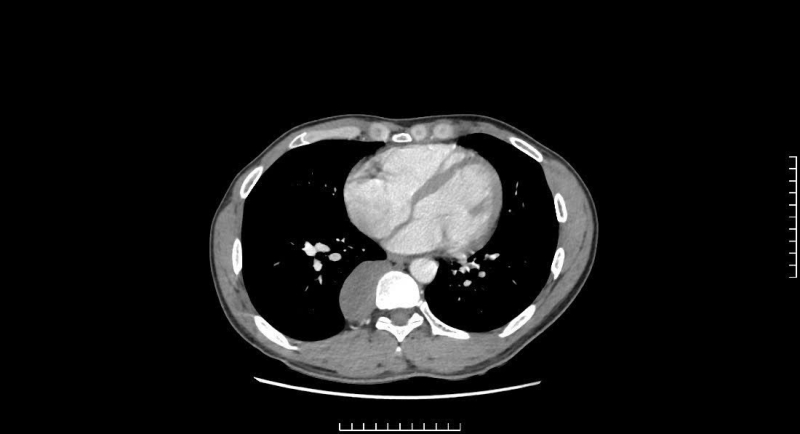

Röntgen av patientens bakre mediastinala tumör.

På sjukhuset undersöktes den unge mannen kliniskt av läkare och utförde djupgående undersökningar. Resultaten av datortomografi och magnetresonanstomografi av bröstkorgen upptäckte en stor tumör (33x90x32 mm) belägen nära ryggraden D7-D11. Efter konsultation diagnostiserade läkarna patienten med en posterior mediastinal tumör, övervakade neuromet och ordinerade endoskopisk thoraxkirurgi.